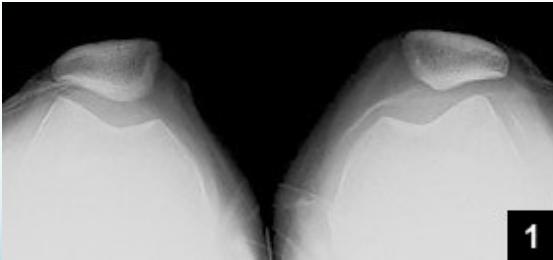

X-ray Studies

Basic Views:

- AP (Anterior-Posterior)

- Lateral

Additional Views:

- AP standing

- Skyline (patellar view)

- Stress films (for ligament assessment)